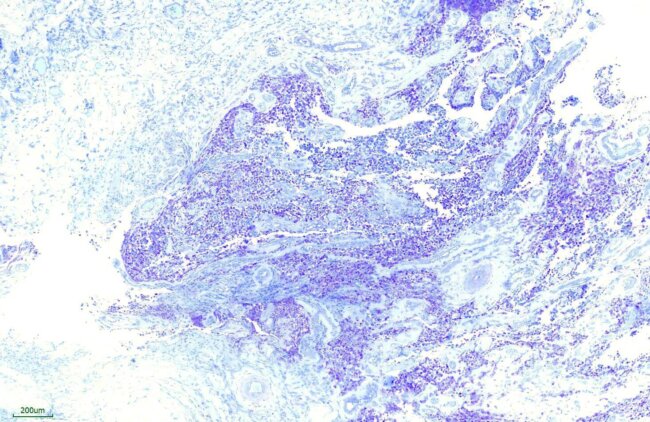

Toluidine blue染色